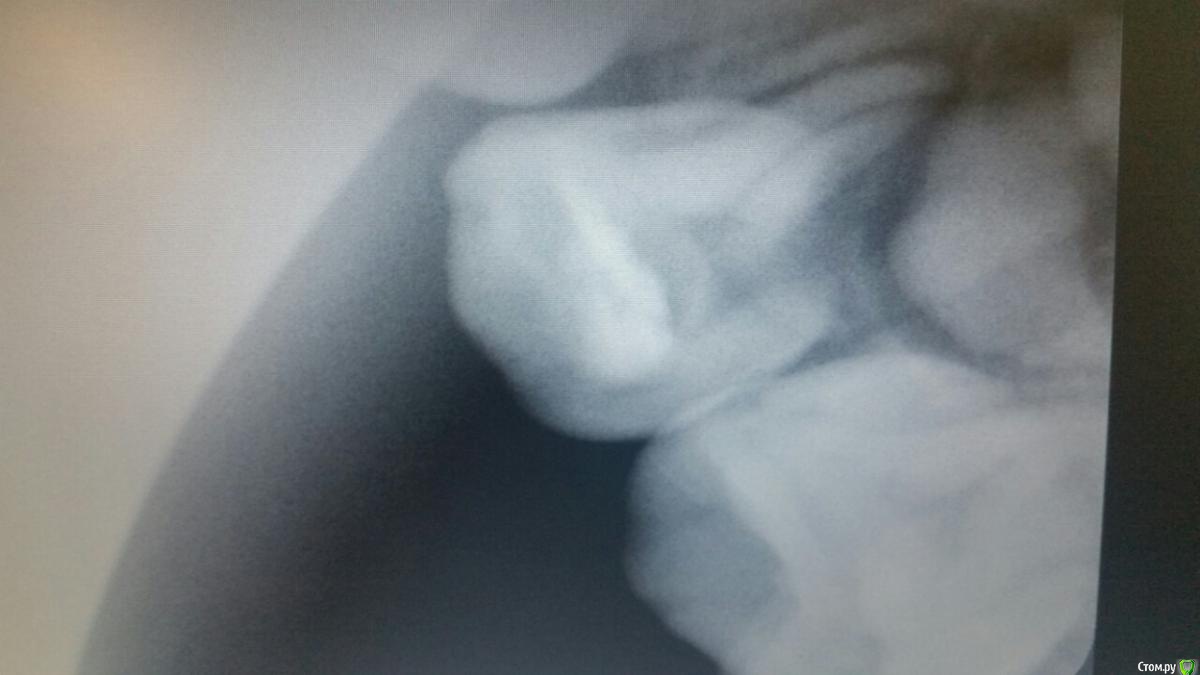

Ребенку скоро 4 года. Чуть более года назад был пролечен поверхностный кариес верхней четверки. В настоящий момент над пролеченным зубом возник небольшой белый "прыщик". Сходили к доктору, удалили старую пломбу, пульпа твердая, живая. Пульпу вскрывать не стали. Сделали снимок. Получили рекомендацию смотреть состояние в динамике. Ребенок ни на что не жалуется, зуб не шатается, при накусывании этим зубом твердых предметов боли не ощущает. Что это периодонтит? Ждать или принимать срочные меры? Спасибо!